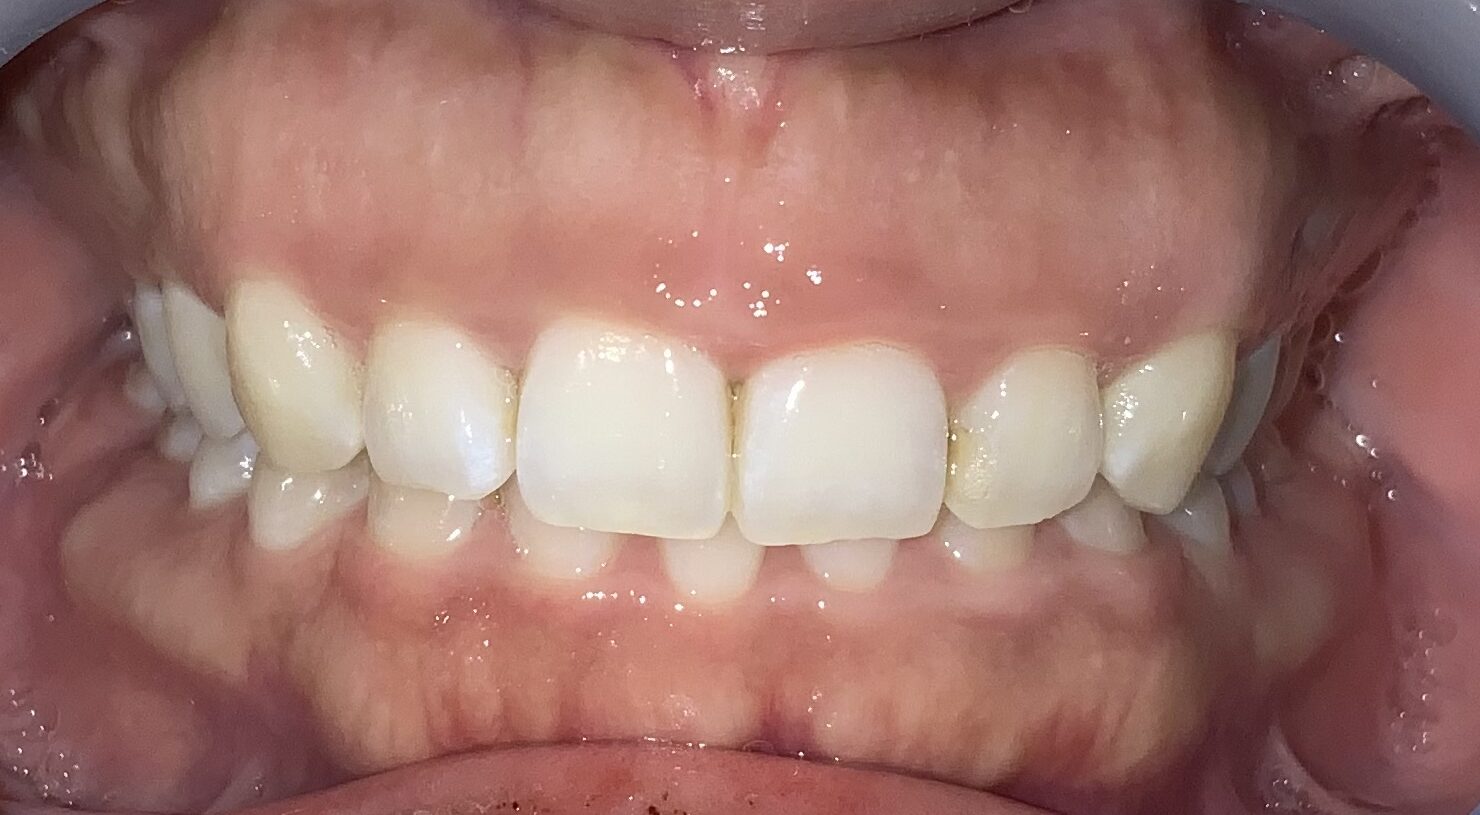

今回の患者様の治療前の状態です。

歯ぐきの長さに比較して、歯が少し小さいですね。歯ぐき自体は健康で綺麗なピンク色をしています。